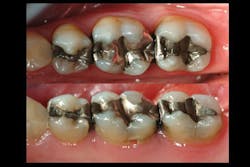

Observe Figures 4 and 5 for the following discussion:

The first molar has a painful, cracked distolingual cusp and lingual caries. Should the amalgam restoration be removed and another intracoronal restoration placed? I see this procedure routinely suggested by some clinicians who promote bonding of the remaining tooth structure to the subsequent direct or indirect restoration. My long-term clinical experience and in vitro research at Clinicians Report Foundation refute that recommendation. Such restorations are only a fraction as strong as a virgin tooth, and I strongly suggest that this procedure eventually results in a doomed restoration and tooth. When more than one-half of the cusp-tip to cusp-tip tooth structure is removed, the tooth has minimal strength remaining and a full-crown or onlay covering all of the remaining cusps is indicated.

Observe the second premolar. It has a deep base in it, but only minimal removal of tooth structure in the isthmus area. If this amalgam were to be replaced with another restoration, what would be appropriate?

Now, observe the second molar. It is still serving well with a 20-year old amalgam in it. If it required replacement for some reason, the same rationale as described for the second premolar is acceptable. However, unless the patient does not desire to remove the amalgam, leave it for another many years. If the patient is concerned about the alleged challenges with amalgam, provide information about the amalgam controversy and let the patient be involved in the decision. The international research on large amalgam restorations shows about twice the longevity of composite in such sized restorations.